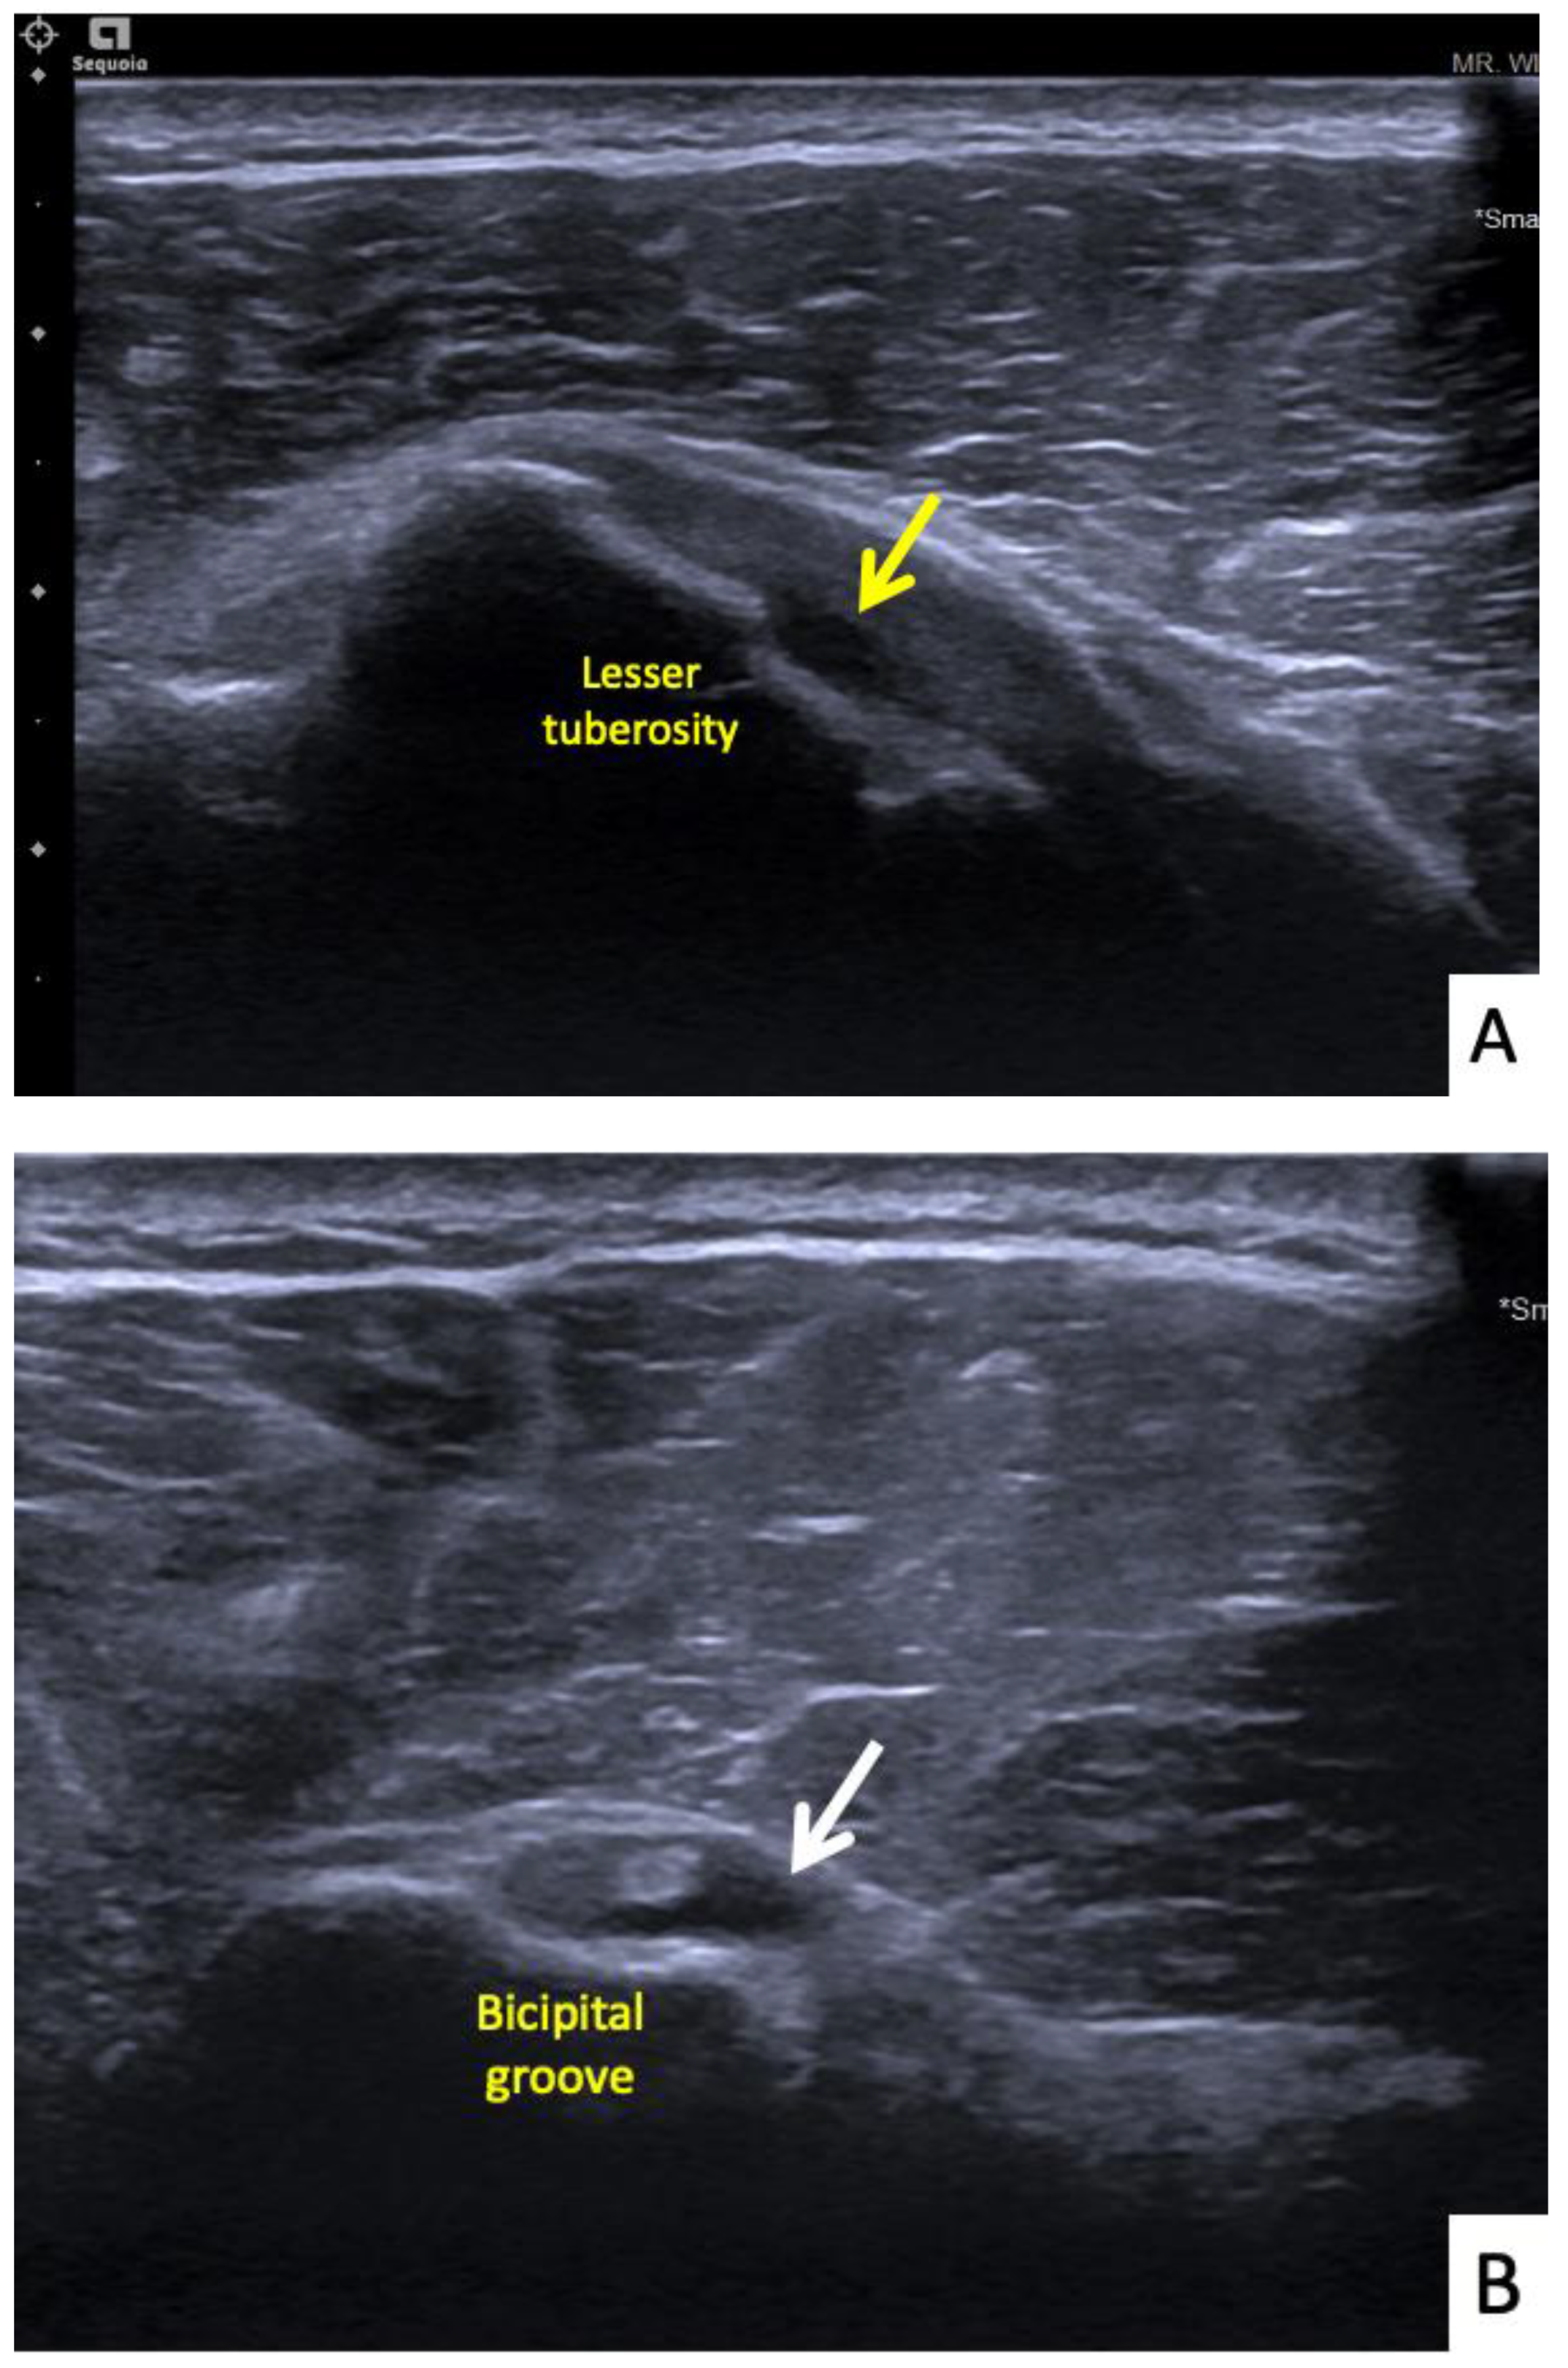

The seventh case was a 64-year-old Thai female who presented with right shoulder pain 9 weeks after a first dose of the AstraZeneca vaccine. The symptoms had begun immediately after the vaccination and gradually gotten worse, to the point that it was painful to complete daily activities and she could not sleep on her right side. In her case, the injection landmark was 1 fingerbreadth below the mid-lateral edge of the acromial process. At the OPD, the physical examination showed limited range of right shoulder motion and pain on the forward motion elevation resistance test and external rotation. Ultrasonography showed calcific tendinopathy of the supraspinatous tendon without bursitis (Figure 8A,B). She was given oral prednisolone (30 mg/day) for 5 days, and she had completely recovered at 1 month.

Figure 8.

Ultrasonographic images of the right shoulder of Patient 7. (A) A sagittal ultrasonographic image over the lesser tuberosity of the right shoulder with the patient in the external rotation position showing a few small calcific deposits (yellow arrows) within the inferior fiber of the subscapularis tendon. (B) A transverse ultrasonographic image of the supraspinatous tendon with the modified Crass position of the right shoulder showing a few small calcific deposits (white arrows) within the mid fiber.